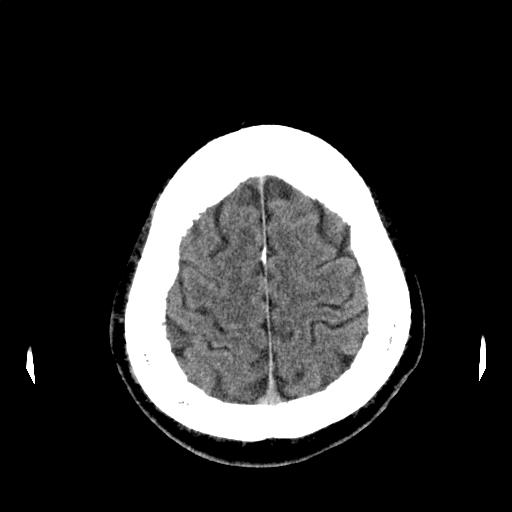

CTスライス画像

(Findings)

頭蓋内に明らかな出血を認めない。

明らかな占拠性病変や広範な脳梗塞を疑う所見は指摘できない。

必要に応じてMRIによる追加評価が望まれる。

両側上顎洞および篩骨洞に少量の軟部陰影を認める。

(Impression)